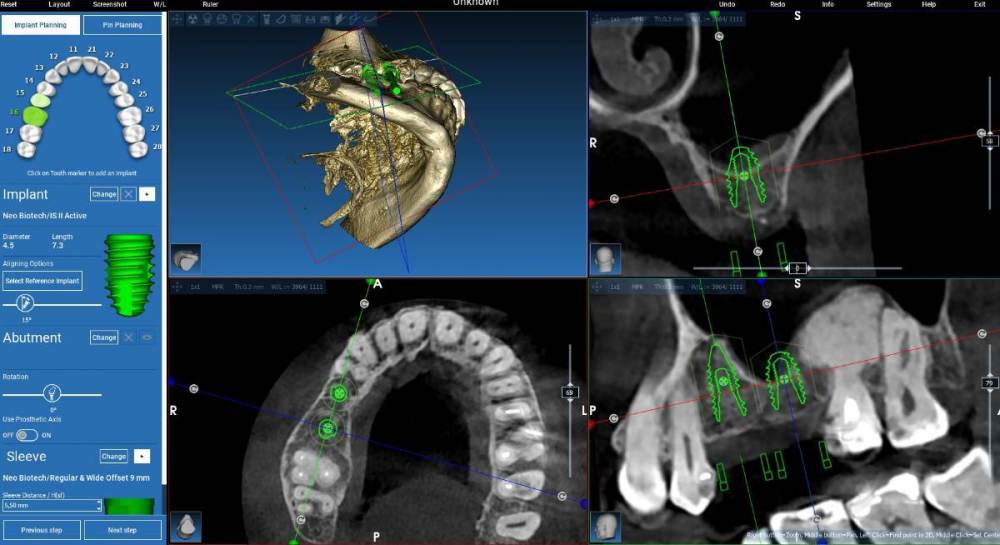

Fin Опубликовано 22 июля, 2023 Поделиться Опубликовано 22 июля, 2023 (изменено) 06.02.2020 в 08:57, Estes сказал: Скажите пожалуйста, что будет и когда это случится, если ставить импланты в кость , когда по ширине кости больше всего на 1 мм, чем диаметр импланта. По длине кости достаточно. То есть имплант диаметр 3.75 ,а кости 4,75. Здравствуйте коллеги. Прошло уже больше двух лет с первого сообщения в этой теме. А вот не могу угомониться. Хотелось бы продублировать данный вопрос спустя 2 года. Правильно ли я понимаю что сейчас минимальная ширина кости должна быть такой что в нее поместится имплантат и не будет оголен. Соблюдение БШ является более важным фактором. Спрашиваю я это потому что после установки имплантата на КТ обнаружил что язычная стенка как буд-то совсем отсутствует. При этом при установке имплантата я полностью наблюдал язычную стенку которая была целой и казалось что толщина кости достаточная. По БШ всего достаточно +установлен МЮ 3.5. Я понимаю что есть огромный фон у имплантата. Но вот в долгосрочной перспективе стоит ли ждать проблемы? Изменено 22 июля, 2023 пользователем Fin Ссылка на комментарий